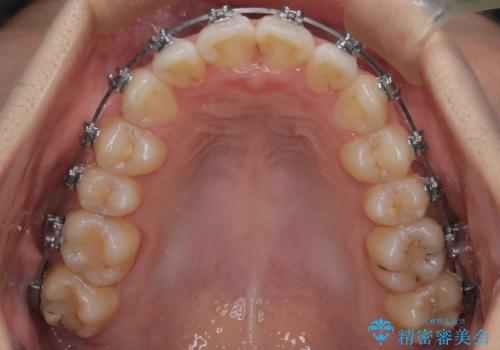

- メタル装置

- 前歯のがたつきを治したいという主訴で来院されました。1年後に転勤の可能性があり短期間での治療を希望されました。今回は非抜歯の治療を計画し、IPRと拡大をし、前歯の叢生を改善しました。

前歯のがたつきを治しながら2番の反対咬合も改善させました。短期間で終了し満足していただけました。